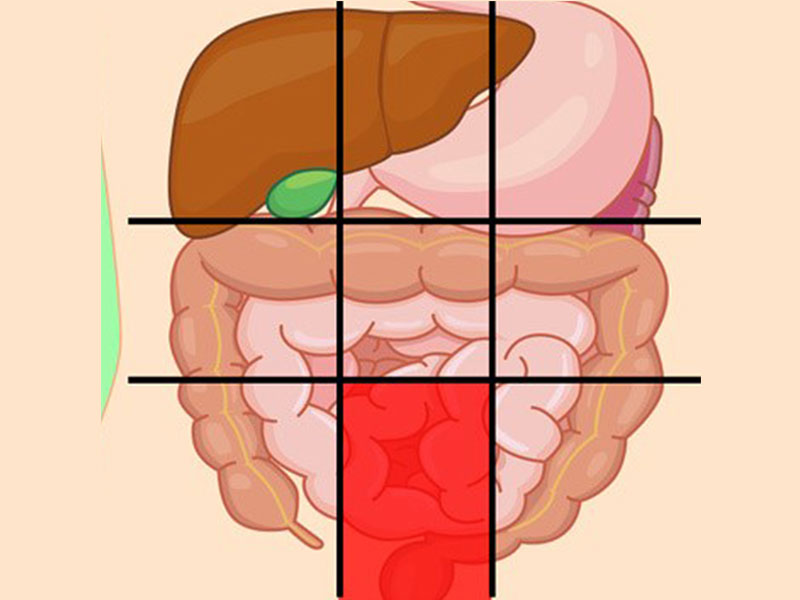

درد شکم در نواحی مختلف نشانه چیست؟

محل درد در شکم ممکن است سرنخی برای علت آن درد باشد که در زیر به بررسی آنها میپردازیم:

درد مرکز شکم نشانه چیست؟

احساس ناراحتی در این بخش از شکم معمولاً با مشکلات در رودهها همراه است.

دلایل ناراحتی در این ناحیه شامل موارد زیر میباشد:

- آپاندیس

- گاستروانتریت (بیماری التهاب معده)

- التهاب روده

- انسداد روده

- جراحت

- اوره (جمع شدن مواد زائد در خون شما)

درد شکم سمت راست پایین نشانه چیست؟

این ناحیه از شکم آپاندیس را شامل میشود و درد آن ممکن است به دلیل مشکلات آپاندیس باشد.

علل رایج درد این بخش:

- آپاندیس

- فتق (هنگامیکه یک ارگان از طریق یک نقطهضعف در عضلات شکم بیرون میزند و برآمده میشود)

- عفونت کلیه

- سرطان

- آنفولانزا